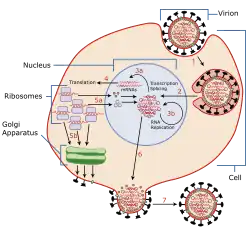

Replicação

Os vírus só são capazes de se replicar em células vivas.[55] A infeção e replicação da gripe é um processo que decorre ao longo de vários estágios. Para ter início, o vírus tem que se ligar e entrar na célula, para então transmitir o seu genoma para um local onde possa produzir novas cópias de proteínas virais e ARN, juntar estes componentes em novas partículas virais e, por último, abandonar a célula hospedeira.[49]

Os vírus da gripe ligam-se, através da hemaglutinina, aos açúcares de ácido siálico na superfície de células epiteliais, geralmente no nariz, garganta ou pulmões dos mamíferos ou no intestino das aves (estágio 1 na imagem).[56] Após a hemaglutinina ser degradada por uma protease, a célula importa o vírus através de endocitose.[57] Ainda não são conhecidos todos os detalhes do processo intracelular. Sabe-se que os viriões convergem para o centro do microtúbulo, interagem com os endossomas ácidos e, finalmente, penetram nos endossomas-alvo para libertar o genoma.[58]

Uma vez no interior da célula, as condições de acidez no endossoma provocam dois eventos. Em primeiro, uma parte da hemaglutinina realiza a fusão do envelope viral com a membrana do vacúolo; em seguida, o canal iónico M2 permite que os protões se movimentem através do envelope viral e acidifiquem o núcleo do vírus, o que faz com que o núcleo se desintegre, libertando assim o ARN viral e as proteínas.[49] As moléculas de ARN viral, proteínas acessórias e a ARN polimerase ARN-dependente são então libertadas para o citoplasma (estágio 2).[59]

Estas proteínas nucleares e o ARN viral foram um complexo que é transportado para o núcleo celular, no qual a ARN polimerase ARN-dependente transcreve o ARN viral complementar de senso positivo (estágios 3a e 3b).[60] O ARN viral é então ou exportado para o citoplasma e traduzido (estágio 4), ou permanece no núcleo. As proteínas virais recém-sintetizadas são então segregadas pelo complexo de Golgi para a superfície da célula (estágio 5b) ou transportadas de volta para o núcleo para ligarem o ARN viral e formar novas partículas de genoma viral (estágio 5a). As restantes proteínas virais exercem diversas ações na célula do hospedeiro, entre elas a degradação do ARNm celular, o uso dos nucleótidos libertados para a síntese de ARNv e a inibição da tradução de ARNm da célula do hospedeiro.[61]

Os ARN virais de senso negativo que formam os genomas de vírus futuros, ARN polimerase ARN-dependente, e outras proteínas virais são montados na forma de um virião. As moléculas de hemaglutinina e neuraminidase agrupam-se numa protuberância da membrana celular. O ARN viral e as proteínas do núcleo viral abandonam o núcleo e penetram nesta protuberância (estágio 6). Os vírus amadurecidos abandonam a célula numa esfera composta por membrana fosfolipídica do hospedeiro, adquirindo hemaglutinina e neuraminidase (estágio 7)..[62] Tal como no início do processo, os vírus aderem à célula através da hemaglutinina. Os vírus amadurecidos separam-se assim que a sua neuraminidase separa os resíduos de ácido siálico da célula do hospedeiro.[56]

Devido à ausência de enzimas com mecanismos de verificação (proofreading), a ARN polimerase ARN-dependente que copia o genoma viral comete um erro a cerca de cada dez mil nucleótidos, o que corresponde ao comprimento aproximado do ARN viral da gripe. Desta forma, a maioria dos vírus de gripe que são fabricados são mutantes, o que causa deriva antigénica, uma pequena alteração nos antígenos da superfície viral ao longo do tempo.[63] A separação do genoma em oito segmentos distintos de ARN viral permite a mistura ou reagrupamento dos ARN virais, no caso de uma célula ser infectada por mais de um tipo de vírus. A rápida alteração de genética viral resultante provoca mudanças antigénicas, que são alterações súbitas de um antígeno para outro. São estas alterações súbitas e significativas que permitem aos vírus infetar novas espécies de hospedeiros ao mesmo tempo que rapidamente ultrapassam qualquer imunidade. Isto é uma das principais causas da existência de pandemias.[53]